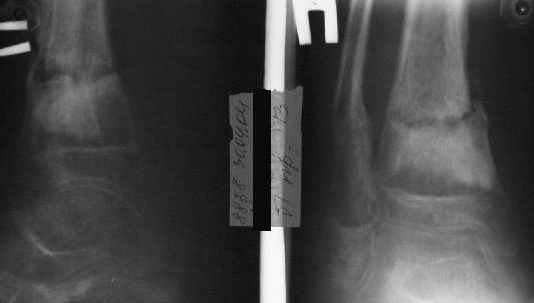

Ребенок 12 лет, поступил после падения с высоты примерно 2,5м.

Перелом костей н\3 правой голени со смещением. Перелом большеберцовой кости можно охарактеризовать как компрессионно-оскольчатый.

Скелетное вытяжение за пяточную кость.

Формирование некроза кожи по задней поверхности н\3 голени~ 1 %, вторичное заживление, кожная пластика. Нейропатия м\берцового нерва (отсутствие активного разгибания 1 пальца) На вытяжении около 8 нед, в дальнейшем в гипсовых повязках ~ 8 мес.

В январе 2005: варусная деформация н\3 голени, болевой с-м, комбинированная контрактура г\стопного сустава, нейропатия м\берцового нерва сохраняется слабость разгибания 1 пальца.

Операции: 1 Клиновидная резекция на вершине деформации м\берцовой кости.

2 Тугоподвижный ложный сустав н\3 б\берцовой кости. Рубцы выполняющие пространство между отломками, канал проксимального отломка иссечены.

Одномоментное устранение деформации, остеосинтез Г-образной пластиной.

Пластика по Хахутову.

Заживление проксимальной части раны вторичным натяжением без нагноения. Рана зажила. Спицы удалены через 1,5 недели после операции.